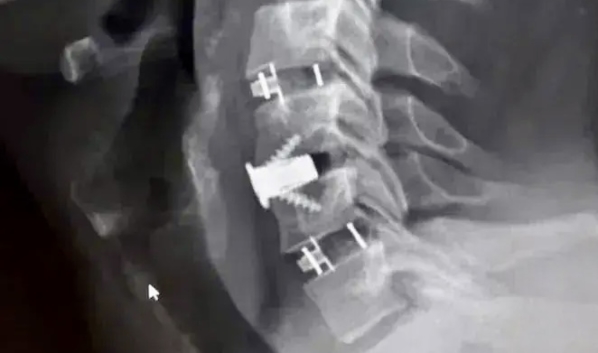

После подготовки мужчине провели операцию с применением комбинированной техники. Бригаду врачей возглавил заведующий нейрохирургическим отделением Павел Юров. Специалисты устранили сдавление и одновременно зафиксировали позвоночник, укрепив его титановыми конструкциями.